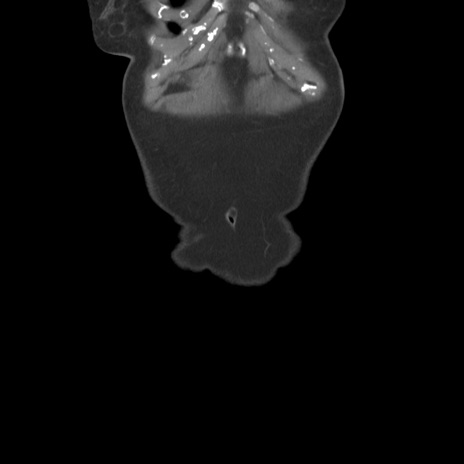

横断像

【症例】80歳代女性

【主訴】下腹部痛

【現病歴】約8時間前より下腹部痛の出現あり、救急外来受診。

【既往歴】両側付属器切除

【身体所見】意識清明、下腹部正中に手術痕あり、その部位に一致して圧痛と反跳痛あり。腸蠕動音は亢進。

【データ】WBC 9300、CRP 0.15